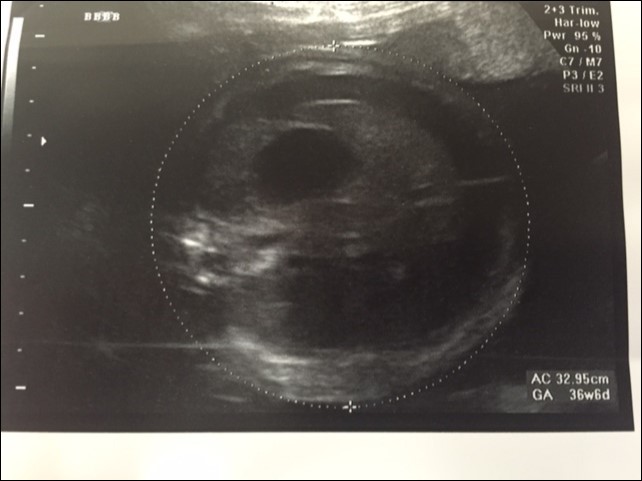

A 37 year old G3P2 female was referred to the pediatric surgical clinic for a twin pregnancy with one of the twins having a large left sided lung mass. The mother had a BMI of 48 and had undergone lap band surgery in the past. The lung mass was detected at 22nd week of gestation and was noted to be homogenous and solid on ultrasound and had a Cyst Volume Ratio (CVR) of 1.4. The twins were dichorionic diamniotic. Twin A had a posterior placenta and twin B (twin with the lung mass) had an anterior placenta. The lesion was located in the left hemi thorax and did not have any associated pleural effusion at first. The differential diagnosis for this lesion included a Stoker Type3 CPAM, a mediastinal teratoma, and a diaphragmatic hernia6. The Twin B was superior in the uterus in a breech position to the right side with a vertical pocket of amniotic fluid measurement of 6.8cm. The Bio Physical Profile score was 10/10. While the middle cerebral artery and ductus venosus dopplers were normal, there was some drop off in the end diastolic flow in the umbilical artery Dopplers. The mother was placed on weekly hi-definition ultrasound follow ups. Echocardiogram showed no structural cardiac defect. Steroids (betamethasone 12mg IM, two doses, 24hours apart) were administered after the development of pleural effusion was noted at the repeat ultrasound performed at 24 weeks and at this point CVR had increased to 1.6. As there was an inadequate response to steroid administration, with the development of a mediastinal shift from the mass effect of the lesion and significant pleural effusion, aspiration of the pleural fluid was performed twice (at weekly intervals during the 26th and 27th week of gestation) with recurrence of the effusion. The pleural fluid analysis showed that it was transudate on both occasions. The volume aspirated on each occasion was about 20 ml. Ascites was also detected and 10 ml of abdominal fluid was aspirated during the second aspiration. It appeared that the fetus was developing hydrops. During the 30th week ultrasound showed a significant mediastinal shift to the right, a large liver with ascites, and increased fetal skin thickness. A thoraco-amniotic shunt was placed at the 30th week of gestation and another course of steroids administered Figure 1 and Figure 2. The significant maternal subcutaneous fat would allow only a direct lateral access into the pleural cavity. The twin and mother were doing well with no symptoms. However, three weeks later, the fetus was able to dislodge the 'double-J' catheter and a second thoraco-amniotic shunt was placed because of recurrence of pleural effusion. While this was successful initially, the combination of the twin pregnancy and interventions led to premature delivery of the twins at 34 weeks gestation. MRI was not considered in the evaluation because of the large BMI.

Figure 1.Antenatal Ultrasound demonstrating the guide wire and shunt in position. The thickness of the amniotic fluid is being measured by the markers.